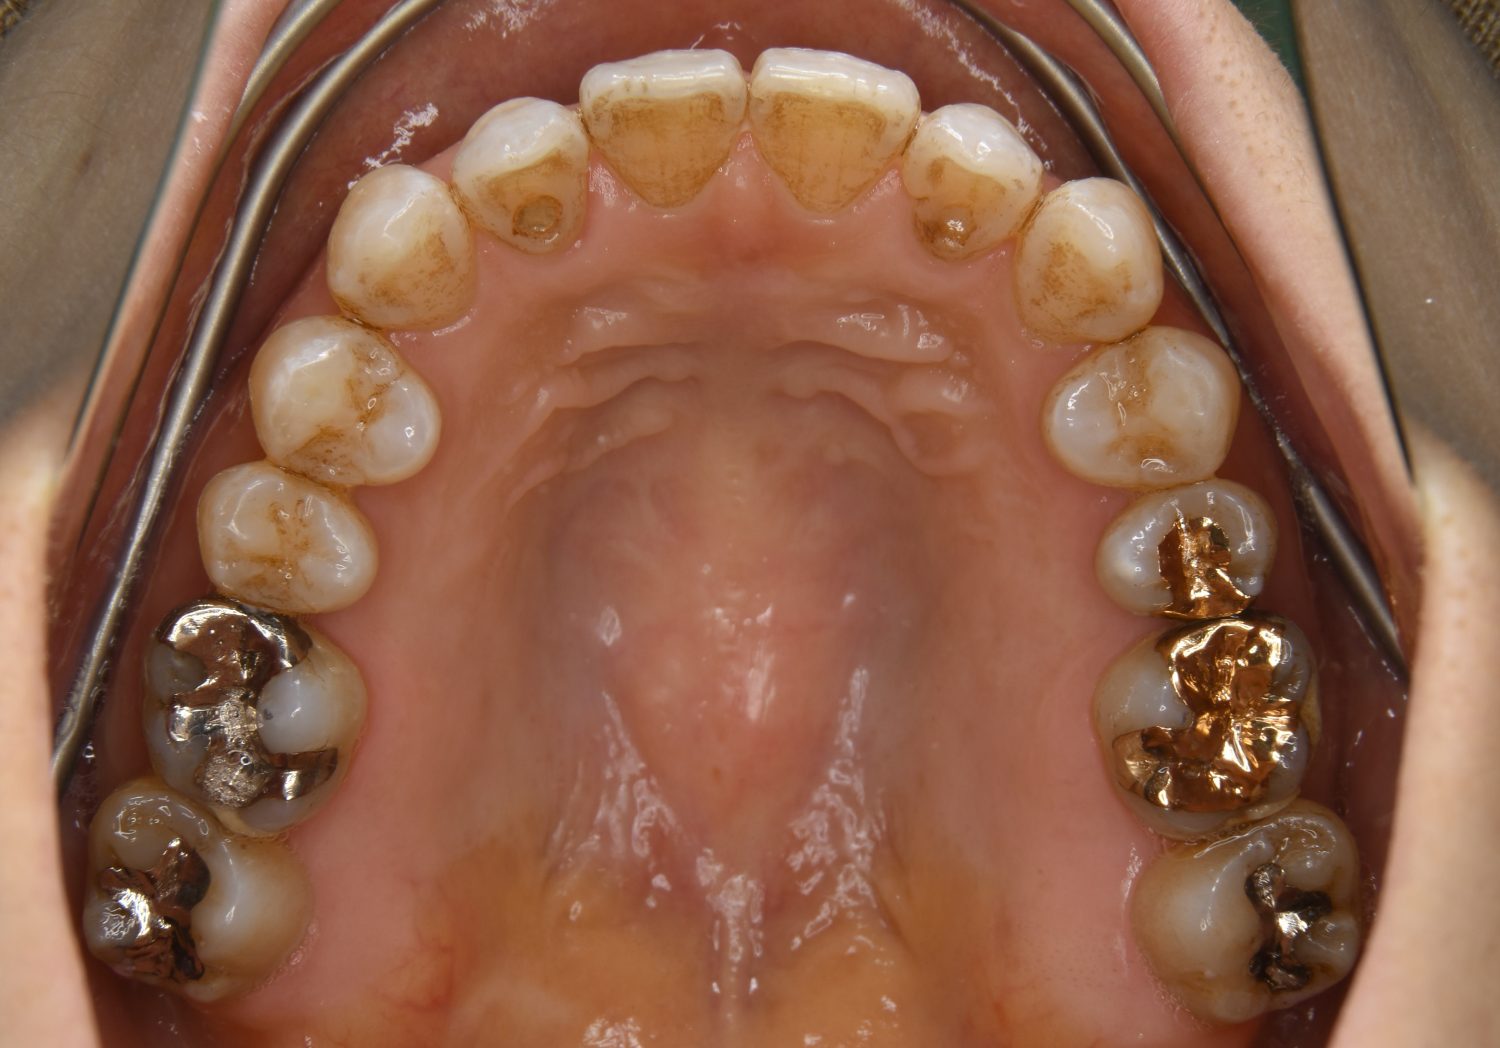

叢生の症例紹介①

Before

主訴

前歯のガタガタが気になる。

治療内容

上顎左側第一小臼歯を抜歯し、アライナー(インビザライン)にて治療を行いました。

治療費

1,150,000 円(税込)

治療期間

23ヶ月

通院回数

13回

想定されたリスク

※歯根吸収、歯肉退縮、歯髄壊死、顎関節症状

※アライナー(インビザライン)は日本の薬機法未承認の矯正装置であり、医薬品副作用被害救済制度の対象外となる場合があります。

左上の側切歯が完全に内側に入り込んでいる状態でした。左上の第一小臼歯のみ抜歯を行い治療を行うことで機能面および審美面を改善しました。